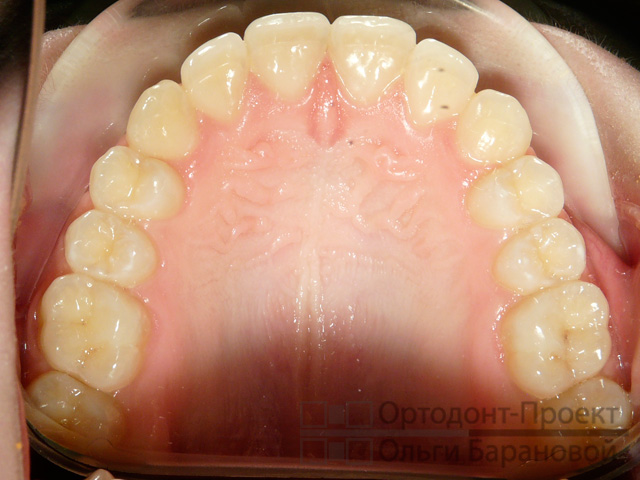

Верхний медиальный резец самый большой из группы резцов . Губная поверхность его коронки выпукла в поперечном и в продольном направлениях . Она имеет 3 небольших продольных . . .

Верхние резцы . Центральный верхний резец . Центральный верхний резец прорезывается (один в квадранте) в возрасте от шести до семи лет, а полное формирование апикальной трети . . .

Размеры зубов человека . Верхние центральные резцы в два раза шире своих антагонистов . Остальные одноименные зубные единицы обладают примерно равными параметрами .

Резцы — передние зубы,прорезаются первыми у детей, применяются для разрезания и захватывания пищи На фото представлен вид зубной единицы в разрезе .

Резцы . Резцами называют элементы, расположенные в центре челюсти . Верхние центральные зубы больше всего подвержены повреждениям в виде трещин на эмали и сколов .

На фото поверхность зуба (желтая), эмалеобразующий слой (синий) и дентин (коричневый) . Резцы: В норме у взрослого человека 8 резцов (11, 12, 21, 22, 31, 32, 41, 42) - центральные . . .

Боковой резец верхней челюсти по размерам уступают центральным, средняя длина зуба 23 мм . (21-25 мм .) . Режущий край образуется при схождении губной и нёбной поверхности .

фото: так выглядит правильный прикус . Форма зубных рядов и их относительные размеры Нижние резцы соприкасаются с небными бугорками верхних . Во время жевания моляры . . .